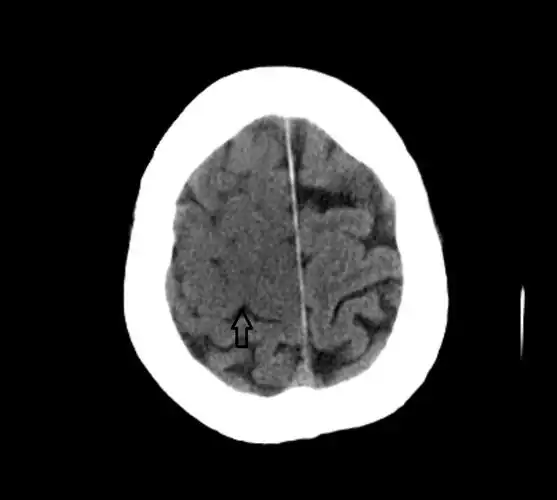

67超急性期大面积脑梗死ct平扫表现